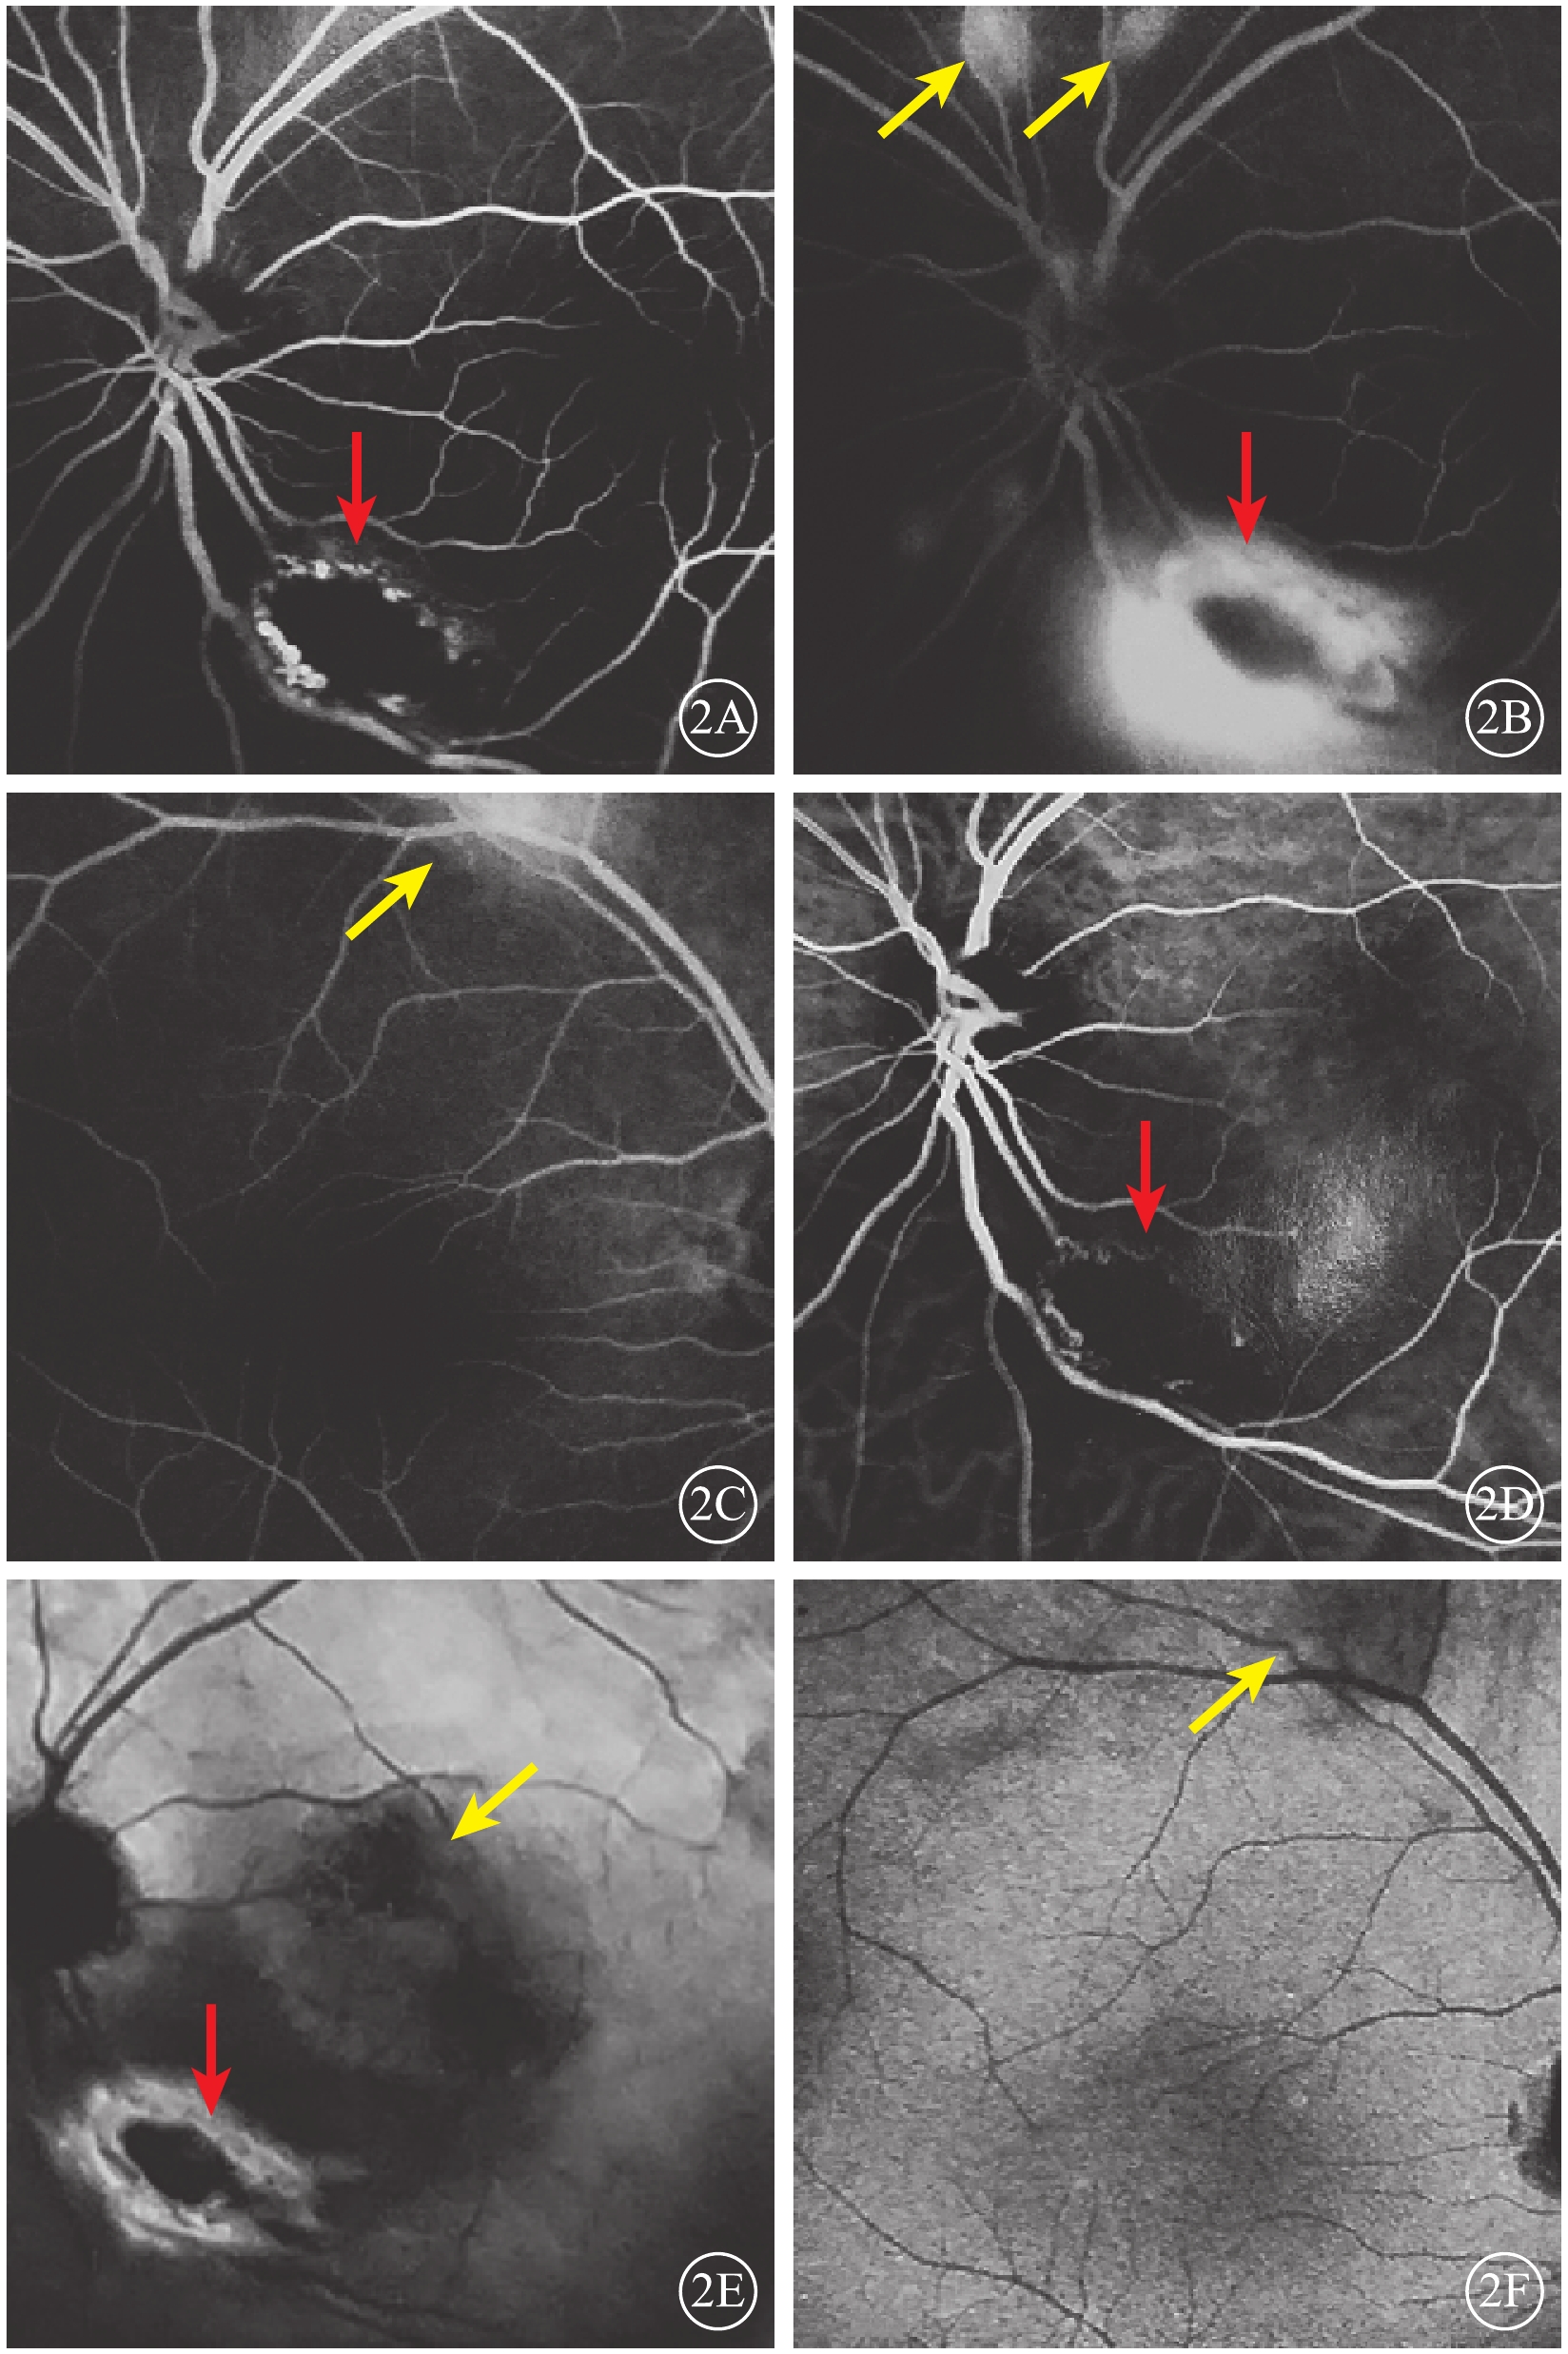

眼底自身熒光(FAF)檢查,左眼視盤顳下約1 DD大小的弱自身熒光(AF),黃斑區呈強AF,范圍約3 DD,鼻側萎縮灶弱AF伴強AF環繞,隱約可見幾處片狀稍強AF(圖3A)。右眼中周部視網膜數處強AF團塊(圖3B)。超廣角眼底彩色照相檢查,左眼視盤顳下1 DD大小團塊狀黃白色病灶,病灶周邊可見血管紆曲;與FFA上病灶對應區域可見數處散在小片狀淡黃色半透明病灶,病灶遮蓋部位視網膜血管稍模糊,黃斑區可見圓形滲出性視網膜脫離區域(圖3C)。右眼上方血管弓處及鼻側周邊及上方周邊可見與左眼相同表現的病灶。

圖3

患者雙眼FAF像及左眼超廣角彩色眼底像。3A.左眼FAF像,黃斑區強熒光(綠箭),顳下病灶弱熒光(紅箭),鼻側萎縮病灶弱熒光伴強熒光環繞(藍箭),隱約可見幾處片狀稍強AF(黃箭);3B.右眼FAF像,中周部視網膜數處強AF團塊(黃箭);3C.左眼超廣角彩色眼底像,視盤顳下可見1 DD大小團塊狀黃白色病灶,病灶周邊部分可見紆曲血管爬行(紅箭),與FFA上病灶對應區域可見數處散在小片狀淡黃色半透明病灶(黃箭),病灶遮蓋部位視網膜血管稍模糊,黃斑區可見圓形滲出性視網膜脫離區域(綠箭),鼻上方可見脫色素斑塊(藍箭)

圖3

患者雙眼FAF像及左眼超廣角彩色眼底像。3A.左眼FAF像,黃斑區強熒光(綠箭),顳下病灶弱熒光(紅箭),鼻側萎縮病灶弱熒光伴強熒光環繞(藍箭),隱約可見幾處片狀稍強AF(黃箭);3B.右眼FAF像,中周部視網膜數處強AF團塊(黃箭);3C.左眼超廣角彩色眼底像,視盤顳下可見1 DD大小團塊狀黃白色病灶,病灶周邊部分可見紆曲血管爬行(紅箭),與FFA上病灶對應區域可見數處散在小片狀淡黃色半透明病灶(黃箭),病灶遮蓋部位視網膜血管稍模糊,黃斑區可見圓形滲出性視網膜脫離區域(綠箭),鼻上方可見脫色素斑塊(藍箭)

眼底自身熒光(FAF)檢查,左眼視盤顳下約1 DD大小的弱自身熒光(AF),黃斑區呈強AF,范圍約3 DD,鼻側萎縮灶弱AF伴強AF環繞,隱約可見幾處片狀稍強AF(圖3A)。右眼中周部視網膜數處強AF團塊(圖3B)。超廣角眼底彩色照相檢查,左眼視盤顳下1 DD大小團塊狀黃白色病灶,病灶周邊可見血管紆曲;與FFA上病灶對應區域可見數處散在小片狀淡黃色半透明病灶,病灶遮蓋部位視網膜血管稍模糊,黃斑區可見圓形滲出性視網膜脫離區域(圖3C)。右眼上方血管弓處及鼻側周邊及上方周邊可見與左眼相同表現的病灶。

圖3

患者雙眼FAF像及左眼超廣角彩色眼底像。3A.左眼FAF像,黃斑區強熒光(綠箭),顳下病灶弱熒光(紅箭),鼻側萎縮病灶弱熒光伴強熒光環繞(藍箭),隱約可見幾處片狀稍強AF(黃箭);3B.右眼FAF像,中周部視網膜數處強AF團塊(黃箭);3C.左眼超廣角彩色眼底像,視盤顳下可見1 DD大小團塊狀黃白色病灶,病灶周邊部分可見紆曲血管爬行(紅箭),與FFA上病灶對應區域可見數處散在小片狀淡黃色半透明病灶(黃箭),病灶遮蓋部位視網膜血管稍模糊,黃斑區可見圓形滲出性視網膜脫離區域(綠箭),鼻上方可見脫色素斑塊(藍箭)

圖3

患者雙眼FAF像及左眼超廣角彩色眼底像。3A.左眼FAF像,黃斑區強熒光(綠箭),顳下病灶弱熒光(紅箭),鼻側萎縮病灶弱熒光伴強熒光環繞(藍箭),隱約可見幾處片狀稍強AF(黃箭);3B.右眼FAF像,中周部視網膜數處強AF團塊(黃箭);3C.左眼超廣角彩色眼底像,視盤顳下可見1 DD大小團塊狀黃白色病灶,病灶周邊部分可見紆曲血管爬行(紅箭),與FFA上病灶對應區域可見數處散在小片狀淡黃色半透明病灶(黃箭),病灶遮蓋部位視網膜血管稍模糊,黃斑區可見圓形滲出性視網膜脫離區域(綠箭),鼻上方可見脫色素斑塊(藍箭)